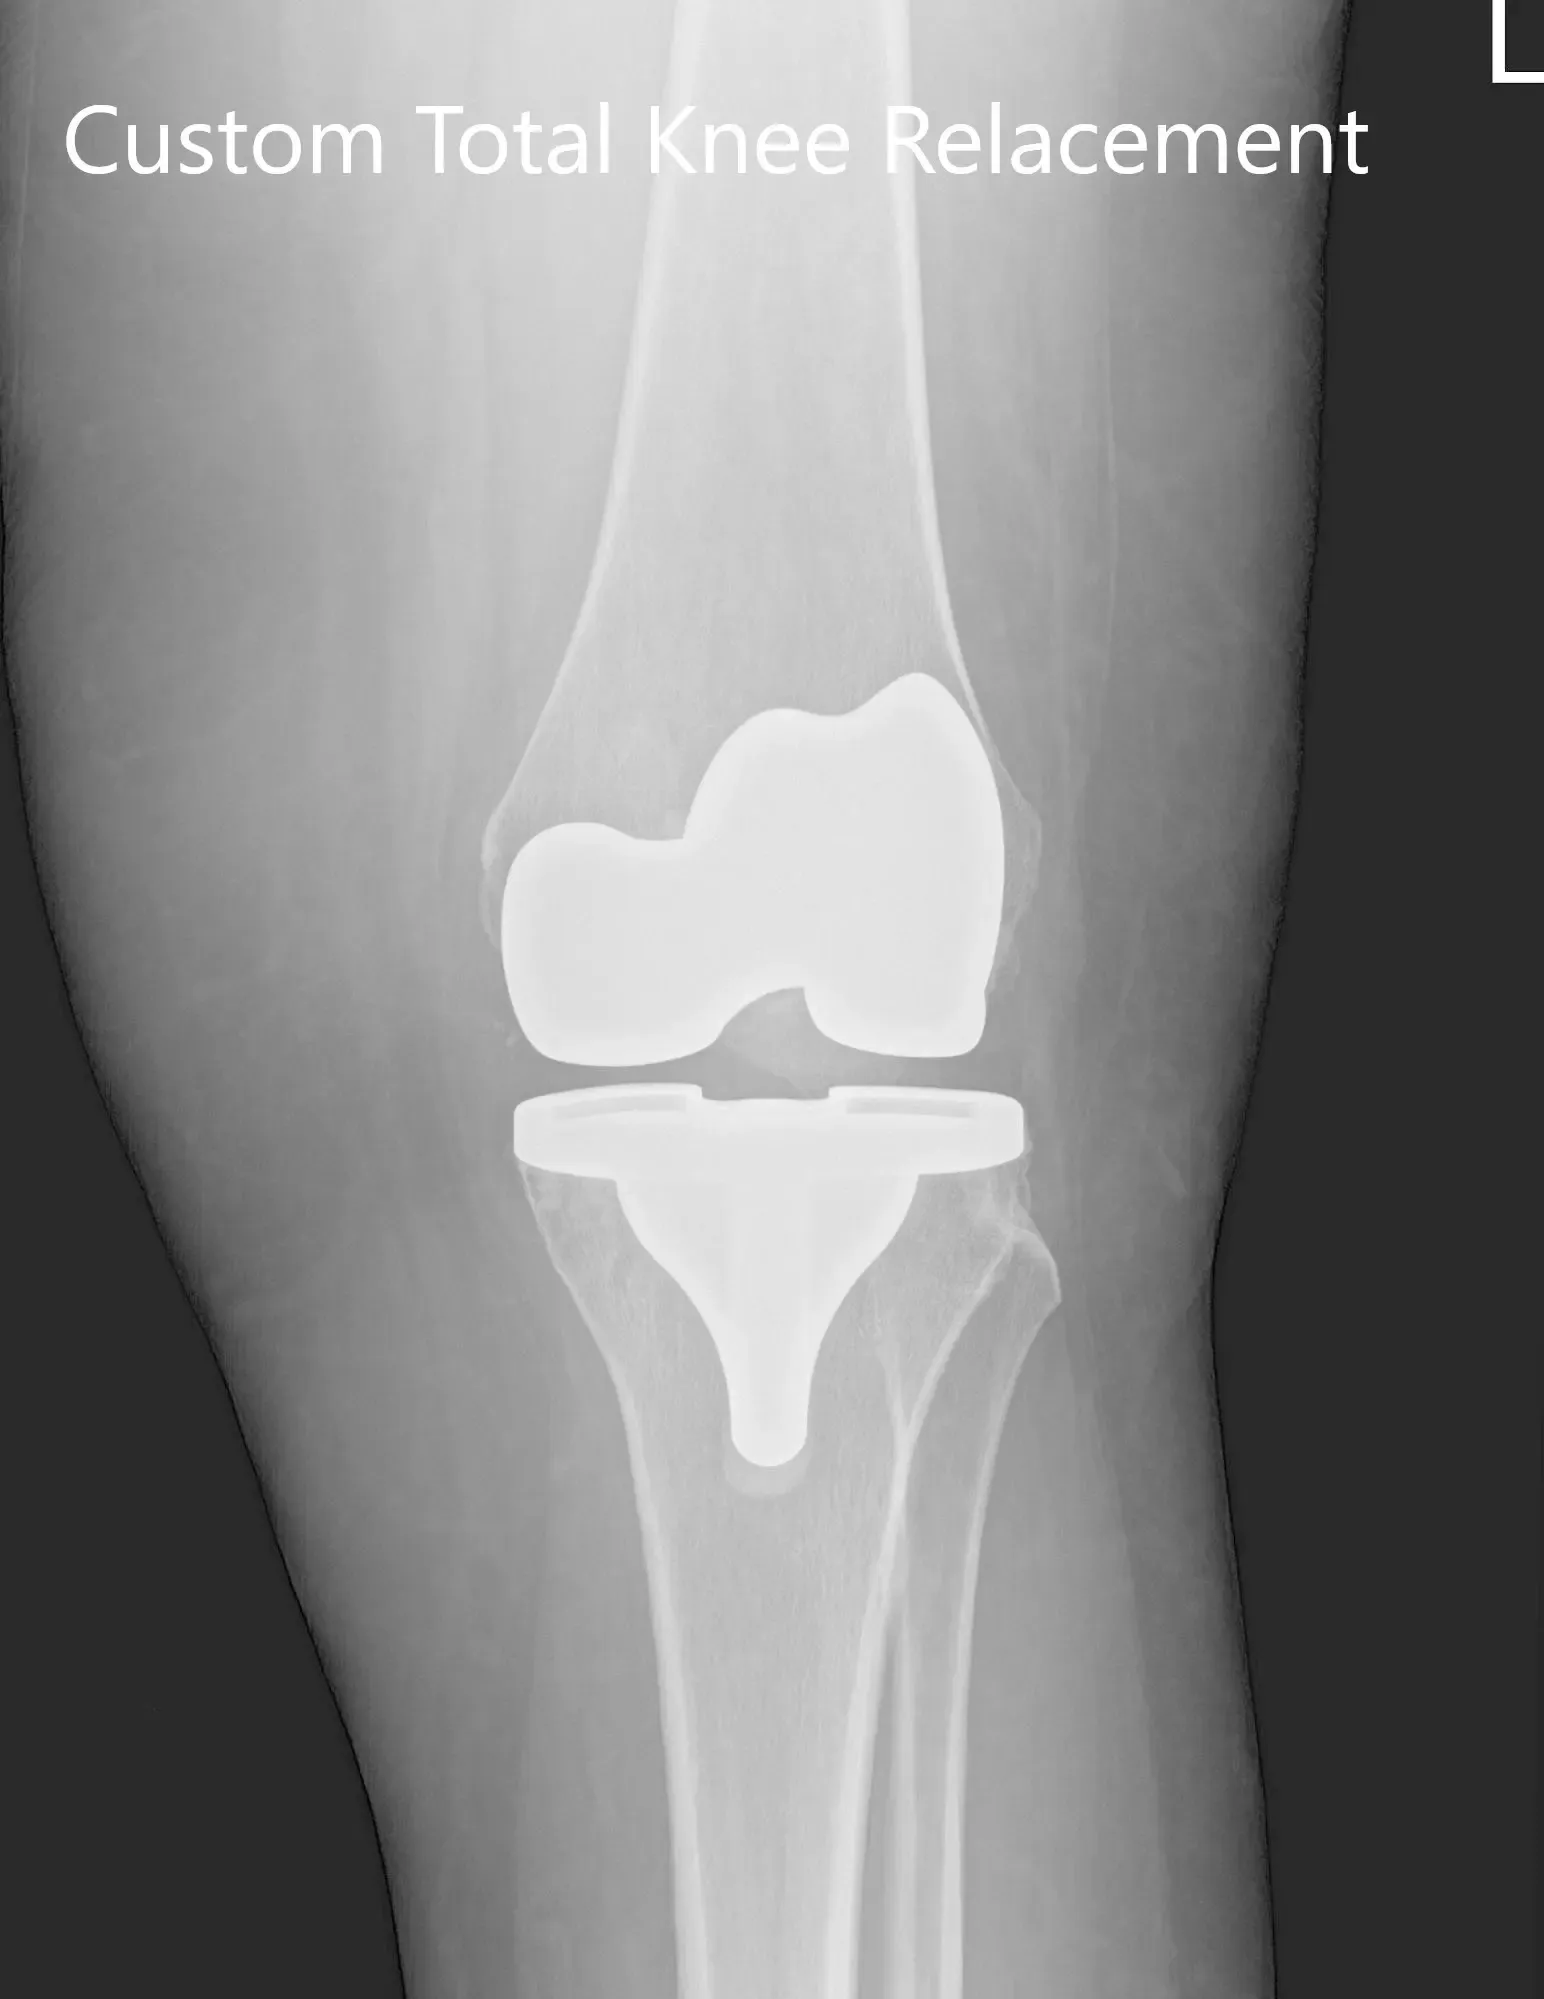

The patient underwent customized left knee arthroplasty

Implant used: Custom femur with a custom tibia and patella (38mmx8.5mm) with 10-mm polyethylene insert.

Three months postoperative X-ray of the left knee showing AP and lateral images.